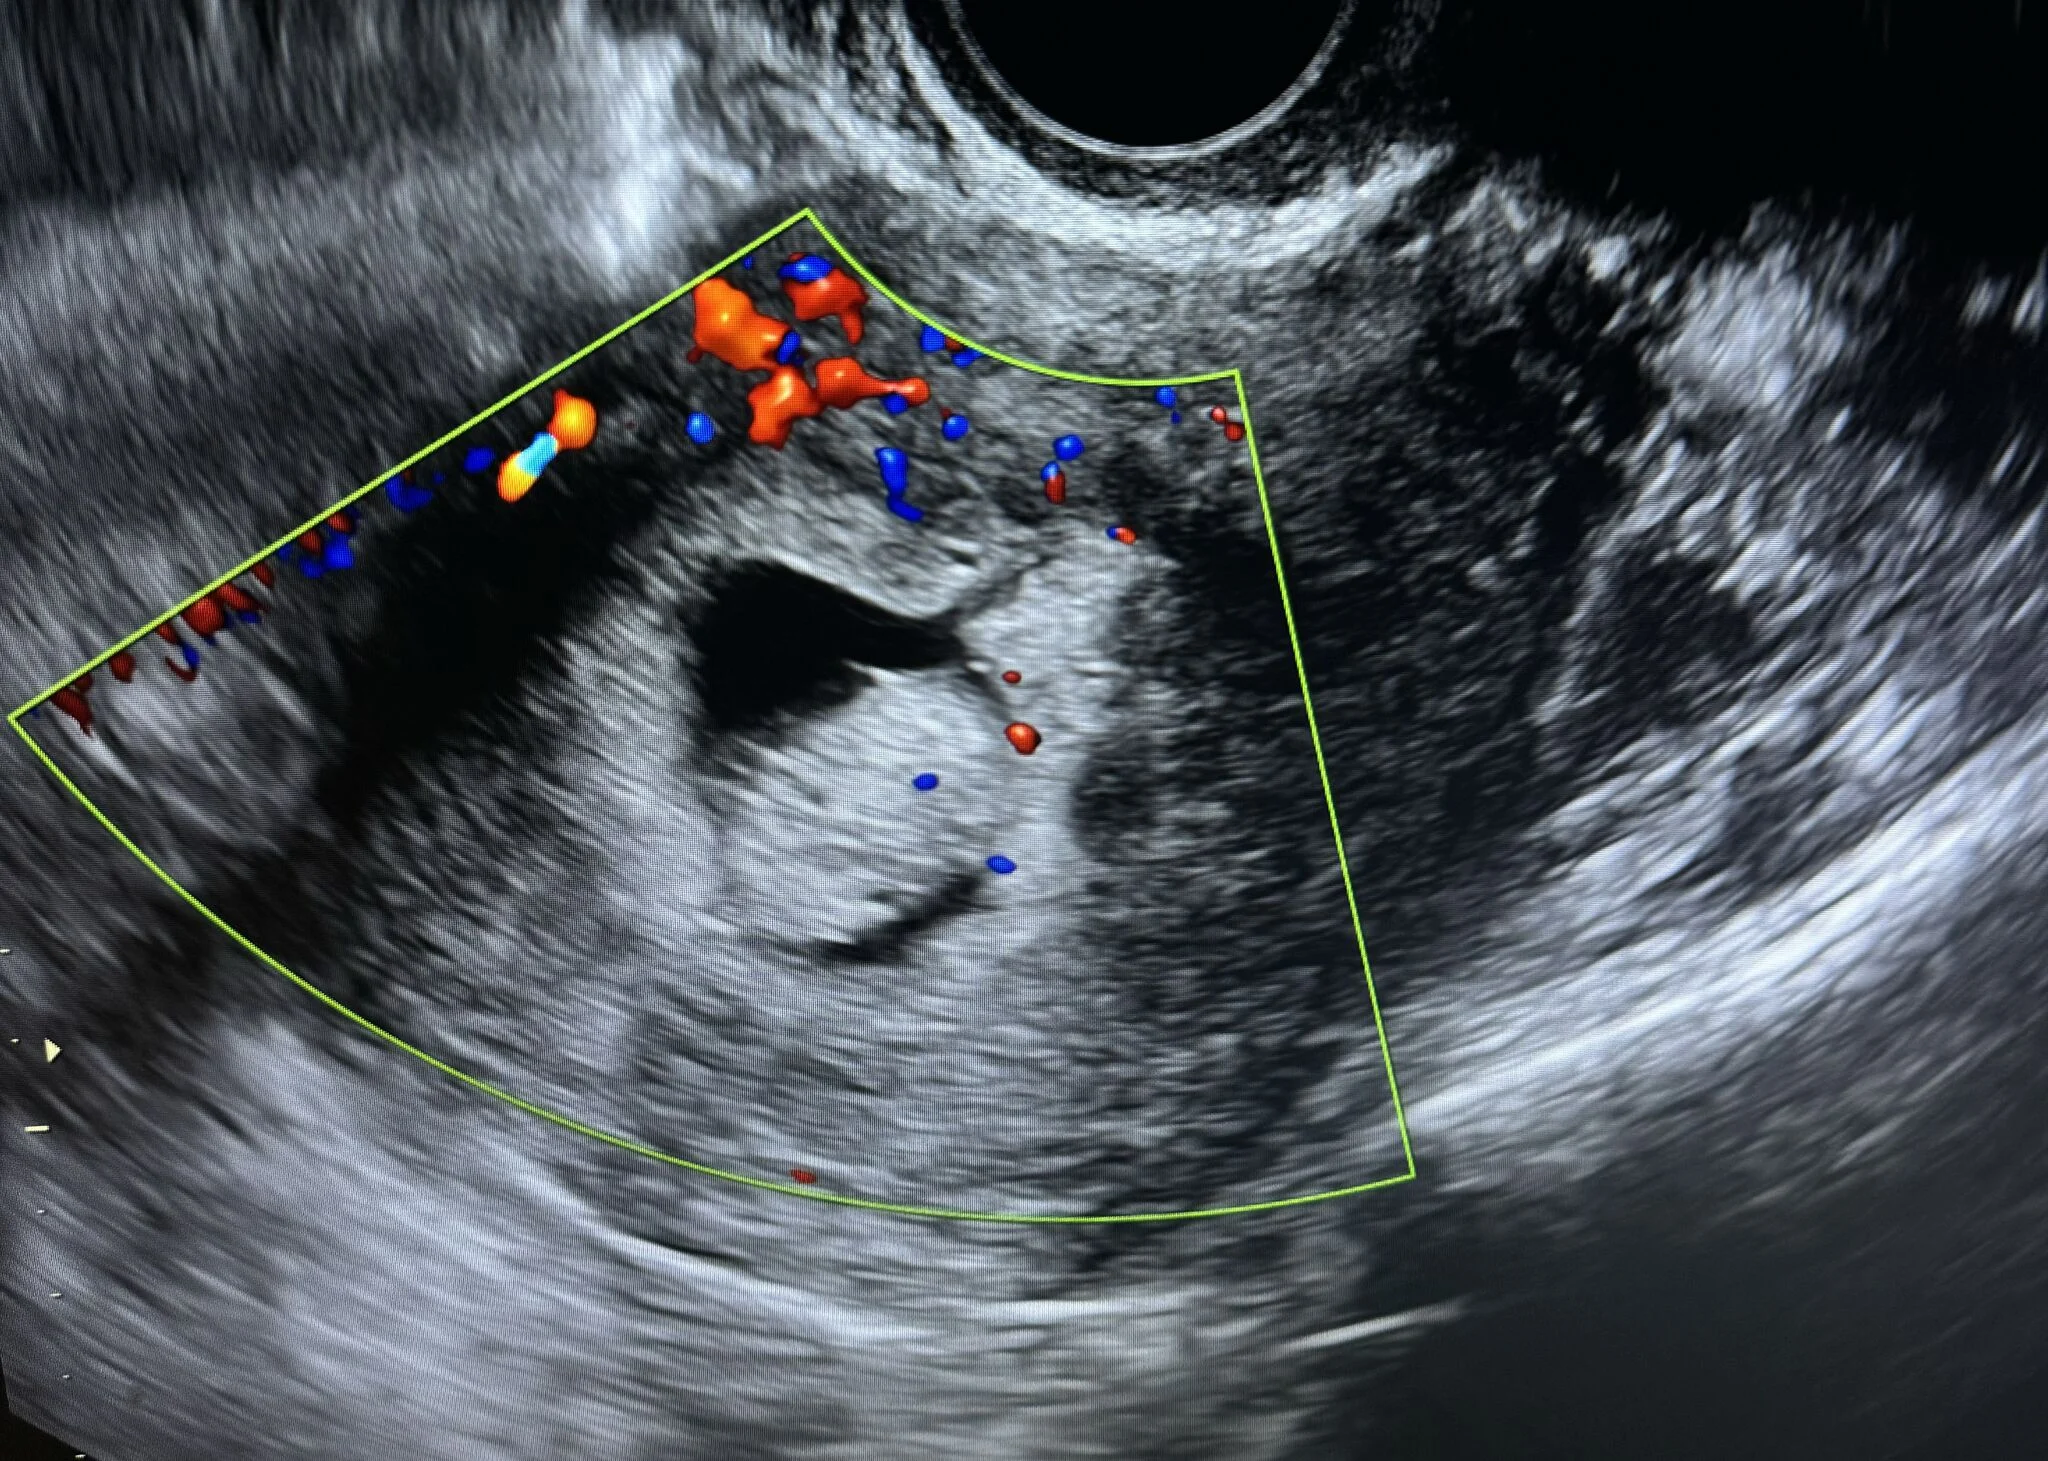

“Case Report: Uterine Polyp

A female patient presented to the clinic with complaints of abnormal uterine bleeding.

Ultrasound examination revealed a large endometrial polyp with notable vascular flow on color Doppler.

Ultrasound Appearance

On ultrasound, an endometrial polyp typically appears as a:

- Well-defined echogenic mass within the endometrial cavity

- Homogeneous texture

- Single central feeding vessel on color Doppler — a key feature distinguishing it from fibroids

Additional features:

- May appear as focal thickening or an oval-shaped lesion

- When using Saline Infusion Sonohysterography (SIS), the polyp can be clearly visualized moving freely within the fluid-filled cavity